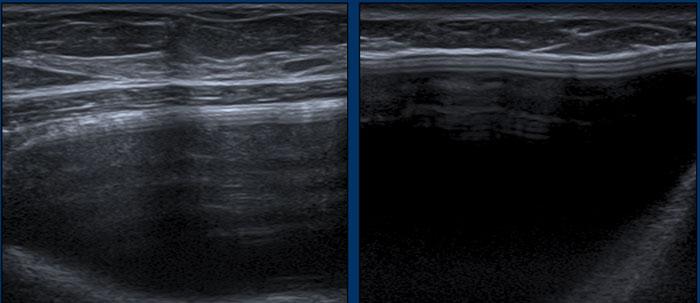

Dấu hiệu Oreo ngược

Vỏ bọc của túi độn có thể được nhìn thấy như một chiếc bánh Oreo lật ngược. Đường trắng đầu tiên là mặt tiếp xúc bên ngoài của vỏ bọc và đường trắng thứ hai là mặt tiếp xúc bên trong giữa vỏ bọc và gel Silicone (mũi tên vàng).

Giữa lớp ngoài của vỏ bọc và bao xơ xung quanh tồn tại một khoang ảo có thể được lấp đầy và giãn rộng.

Bao xơ được nhìn thấy tách biệt khỏi vỏ bọc như một đường trắng riêng biệt nằm phía trước vỏ bọc (mũi tên trắng).

Vỏ bọc và bao xơ cùng nhau được gọi là phức hợp vỏ bọc-bao xơ.

Đây là túi độn ngực ở vị trí dưới cơ ngực.

Cơ ngực lớn được nhìn thấy ở phía trước túi độn.

Về phía đuôi, cơ ngực lớn mỏng dần và sẽ khó quan sát hơn.

Dấu hiệu bậc thang (Step off sign)

Dấu hiệu bậc thang là một xảo ảnh gây ra bởi tốc độ truyền âm thấp hơn của sóng siêu âm qua Silicone (970 m/giây trong gel Silicone so với 1540 m/giây qua nước).

Hệ quả là thành ngực có vẻ sâu hơn ở vị trí tương ứng với túi độn.

Xảo ảnh này không xuất hiện trong các túi độn chứa nước muối sinh lý.